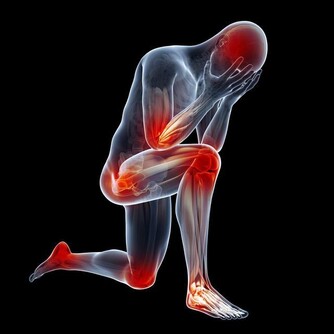

五、腳關節疼痛

如果我們經常感覺我們的腳趾頭出現疼痛的症狀,並且疼痛的同時還會出現腫脹和僵硬的情況,那麼這時候,就應該注意了,我們很有可能感染了風濕性關節炎,往往風濕性關節炎的起先症狀會反應在我們的腳趾頭的關節上。

這時候,我們可以到醫院是做個檢查來確定關節疼痛的具體原因,萬一確診是風濕性關節炎的話,我們可以使用藥物和合理的膳食來治愈風濕性關節炎,幫助我們重新獲得健康的身體。